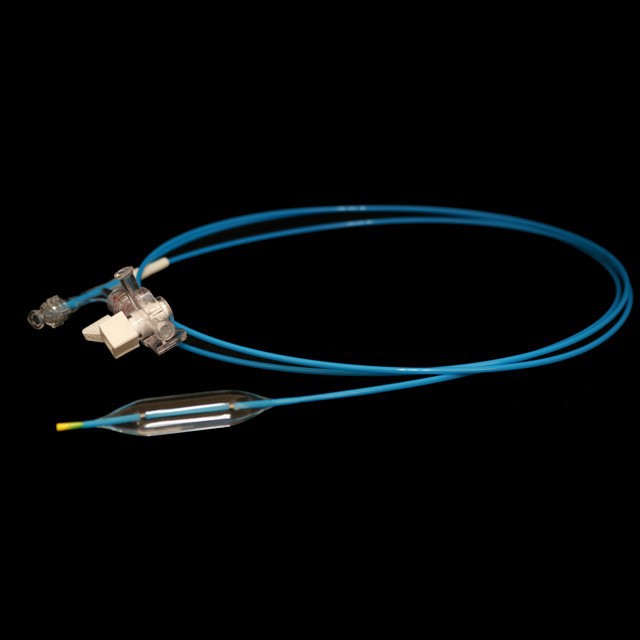

And તે એન્ડોસ્કોપ્સ હેઠળ પાચક ટ્રેક્ટ કડકતાના વિક્ષેપ કામગીરીમાં પુખ્ત વયના અને કિશોરો માટે યોગ્ય છે .}

The ટ્યુબની શ્રેષ્ઠ ડિઝાઇન તેને સરળ અને સારી સ્થિતિસ્થાપકતા, મજબૂત વળી જતું પ્રતિકાર અને સરળ પસારતા બનાવે છે .

● પ્રી-ઇનપુટ 0 . 035 "સોફ્ટ ટીપ અને માર્ક સાથે માર્ગદર્શિકા વાયર, જે અંદરના માર્ગદર્શિકા વાયરની લંબાઈનો અંદાજ કા .વા માટે સરળ છે.